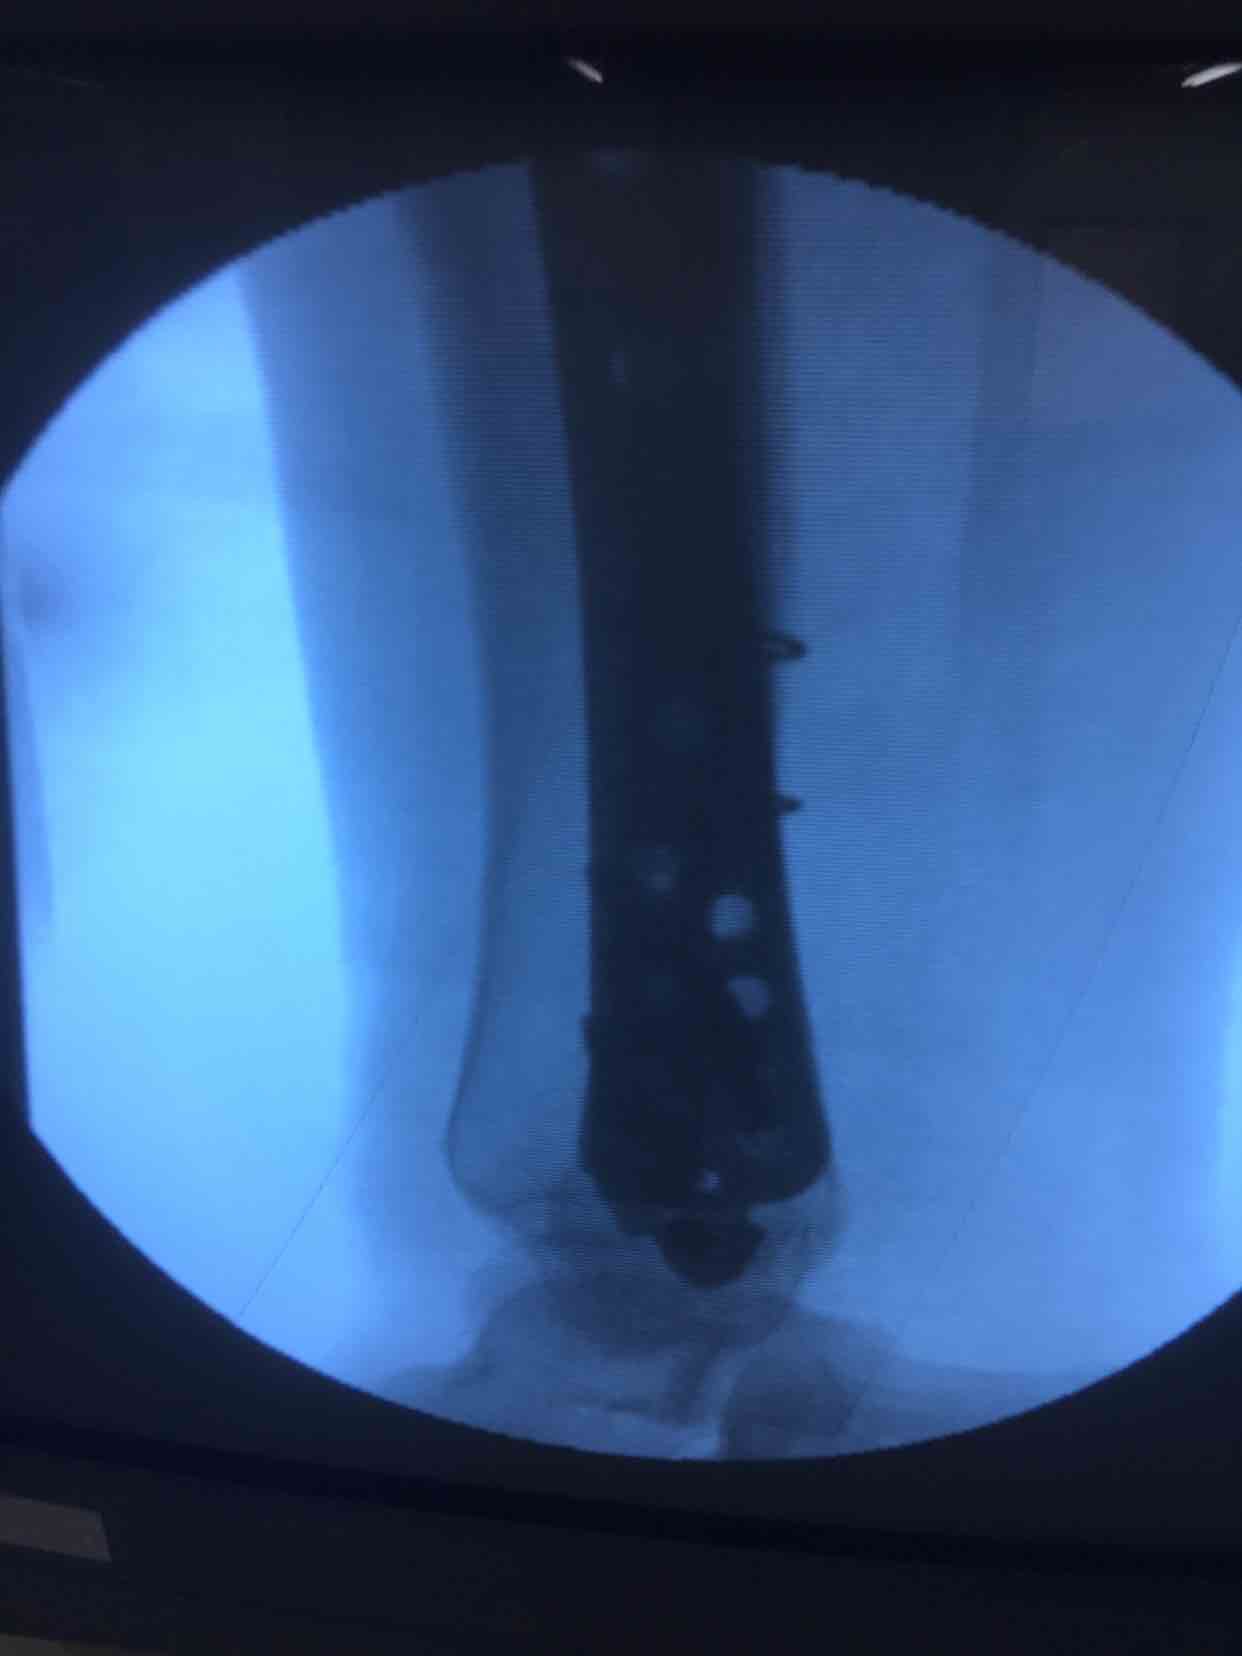

诊断右胫腓骨粉碎性骨折

在腰麻下行切开复位内固定术,术后抗炎,消肿等处理。

术后半年复查